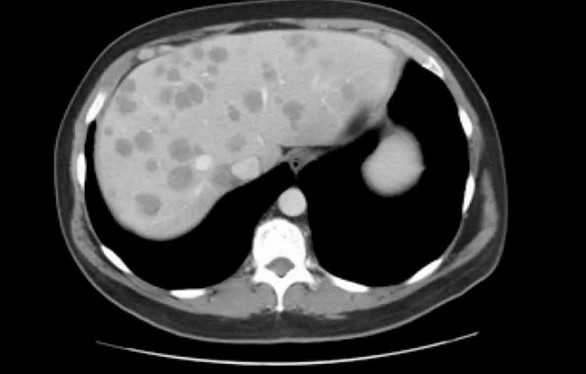

рис. 1-3 По данным МСКТ органов брюшной полости с в/в контрастированием: признаки объёмного образования на уровне мезогастрия (среднего этажа брюшной полости), связанное со стенкой тонкой кишки (дивертикул подвздошной кишки?).

Клинический диагноз:

Основной: Дивертикул подвздошной кишки.

Осложнения: перфорация дивертикула подвздошной кишки. Абсцесс брюшной полости.

Пациентка оперирована в плановом порядке в объеме лапароскопически-ассистированной резекции тонкой кишки. Лапароскопическойхолецистэктомии. Аппендектомии. Энтероэнтеростомии. Дренирования брюшной полости.

При проведении операции у пациентки было выявлено объемное образование, расположенное в мезогастрии с вовлечением стенки тощей кишки на нескольких участках. При вскрытии данного образования было выявлено наличие инородного тела (марлевая салфетка).

Из данного клинического случая можно сделать вывод:

для диагностики инородного тела крайне важным является сбор анамнеза с указанием предшествующей хирургической операции. При подозрении на наличие у пациента инородного тела МСКТ позволяет визуализировать в образовании пузырьки газа диаметром от 1,5 мм, оценить степень изменений в окружающей жировой клетчатке, взаимоотношение инородного тела с прилежащими органами, косвенно оценить наличие кровотока в подозрительном образовании.